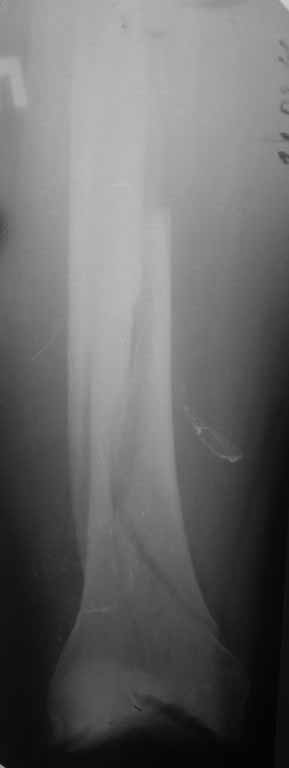

Уважаемые коллеги! 5.08.11 синтез бедренной кости пластиной LCP для дистального бедра.

Прошу совета. П-ка, 59 лет, автодорожная травма, перелом винтообразный н/3 левой бедренной кости. Планировалась закрытая репозиция и малоинвазивный доступ. по ходу операции пришлось немного открыть зону перелома для репозиции. Под контролем ЭОП вроде на столе смещение небольшое было и по оси терпимо. Сделали рентген контроль и получили вот картину. Еще обломилась головка кортикального винта. Синтез то стабильный. Только смещение не только не устранили, но кажется еще чуть больше стало (не могу) первичный снимок сделать). Склонен к ресинтезу и исправлению смещения из расширенного доступа. Как лучше выполнить репозицию? Какие можно использовать приемы репозиции? Спасибо.

конечно реостеосинтез, у Вас нижнии шуруп в линии перелома.

тип 32А1 - межфрагментарная компрессия стягивающим винтом + нейтрализующая пластина(если говорить о накостном остеосинтезе, кроме того пластинку бы подлинее этак на см 5). Ну а лучше - гвоздь с блокированием - закрыто, стабильно, с нагрузкой в послеоперационном периоде.

Коллега,для адекватной оценки перелома необходимо предоставлять предоперационные и послеоперационные снимки в двух проекциях. Насколько возможно судить по маленькой картинке прямой проекции, на первый взгляд тут простой винтообразный перелом 32-А1. В таком случае самый стабильный вариант накостного остеосинтеза - это стягивающий винт перепендикулярно линии перелома и нейтрализирующая пластина. Особых показаний к малоинвазивному мостовидному остеосинтезу нет, т.к. при нем ниже стабильность фиксации, и все микродвижения сконтрентрируются в сравнительно небольшой зоне перелома, что приведет к большим смещающим силам. Однако, если присмотрется, на снимке видно что линия перелома продолжается до начала медиального мыщелка, поэтому скорее всего это клиновидным перелом со спиральным клином 32-В1. В таких случаях возможно выполнение мостовидного синтеза, однако в данном случае дистальная часть клина не смещена относительно дистального конца бедренной кости, таким образом, мне кажется, биомеханически ситуация представляет собой среднее между А1 и чистым В1. Смещающие усилия концентрируются в проксимальной части перелома, тогда как в дистальной несмещенной части они минимальны, в т.ч. из-за интактной надкостницы. Поэтому в данном конкретном случае, при невозможности выполнения интрамедуллярного блокирующего остеосинтеза, я бы выполнил остеосинтез с двумя стягивающими винтами (с рассверливанием ближнего кортикала сверлом большего диаметра) и нейтрализирующего остеосинтеза пластиной. Причем пластина могла бы быть даже обычная.

На представленных снимках, репозиции нет, есть вальгус. Полагаю фиксация не стабильна. Перелом может и срастется, но это будет долго и без нагрузки. Если бы была использована обычная пластина, можно было бы попробовать малоинвазивно подтянуть дистальный отломок и зафиксиривовать парой винтов. Однако примененные блокирующие винты не позволят этого сделать. Как вариант, возможно открытся снизу удалить винты, сделать небольшой доступ в зоне перелома (или попробовать закрыто) ввести 1-2 винта для фиксации клина, и перепровести блокирующие дистальные винты. В любом случае, стабильность при любом из этих вариантов будет заведомо ниже чем при стягивающих винтах + нейтрализирующей пластине. Удачи.